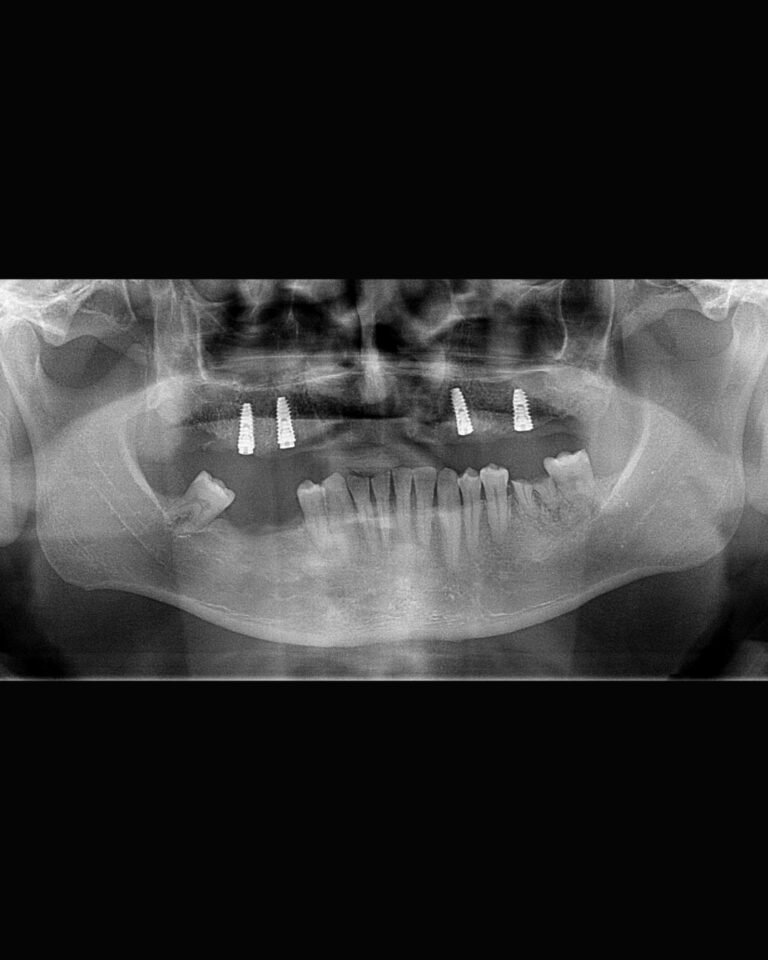

Numero de implantes

En el maxilar superior se necesitan al menos 4 implantes más sus respectivos pilares para lograr resultados óptimos.

En la mandíbula se requieren al menos 2 implantes, idealmente 4 para obtener un tratamiento predecible.

Casos clínicos

Para una sobredentadura sobre pilares locator en el sector superior maxilar se recomiendan 4 implantes como mínimo.

En el sector inferior se recomiendan 2 implantes como mínimo, idealmente 4.